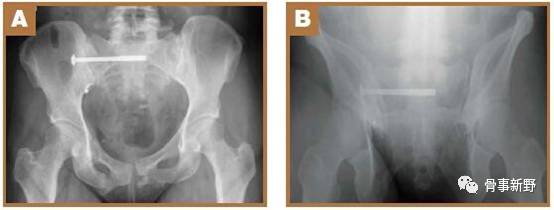

(2)透视:C形臂放在患侧,术中透视骨盆正位、入口位、出口位及侧位。

侧位:a1、a2代表双侧坐骨大孔;b1、b2:代表骶骨翼

(4)骶髂螺钉的定位:导针进针点在髂后上、下嵴之间,髂后上嵴外约2横指、坐骨大切迹上方2横指。透视确认入针点,正位、入口位及出口位满意后(在正位图像中导针尖部位于在S1椎体阴影中,出口位导针指向S1椎体中间1/3份,导针位于S1椎体上终板附件的骨质最厚处)。打入导针到中线,一共穿过3层皮质骨,透视位置确认后进行钻孔。